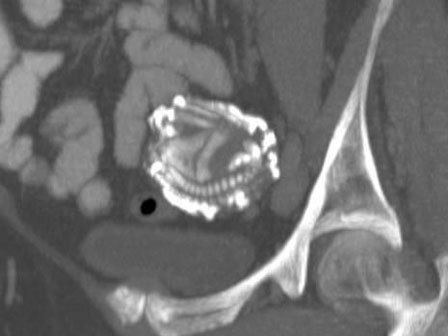

Bụng của bé sơ sinh to bất thường, bác sĩ "kinh hoàng" khi xem kết quả X-quang, lúc phẫu thuật lại càng choáng váng

Theo các bác sĩ, đây là một trường hợp cực kỳ hiếm gặp, với tỉ lệ 1/500.000 ca sinh